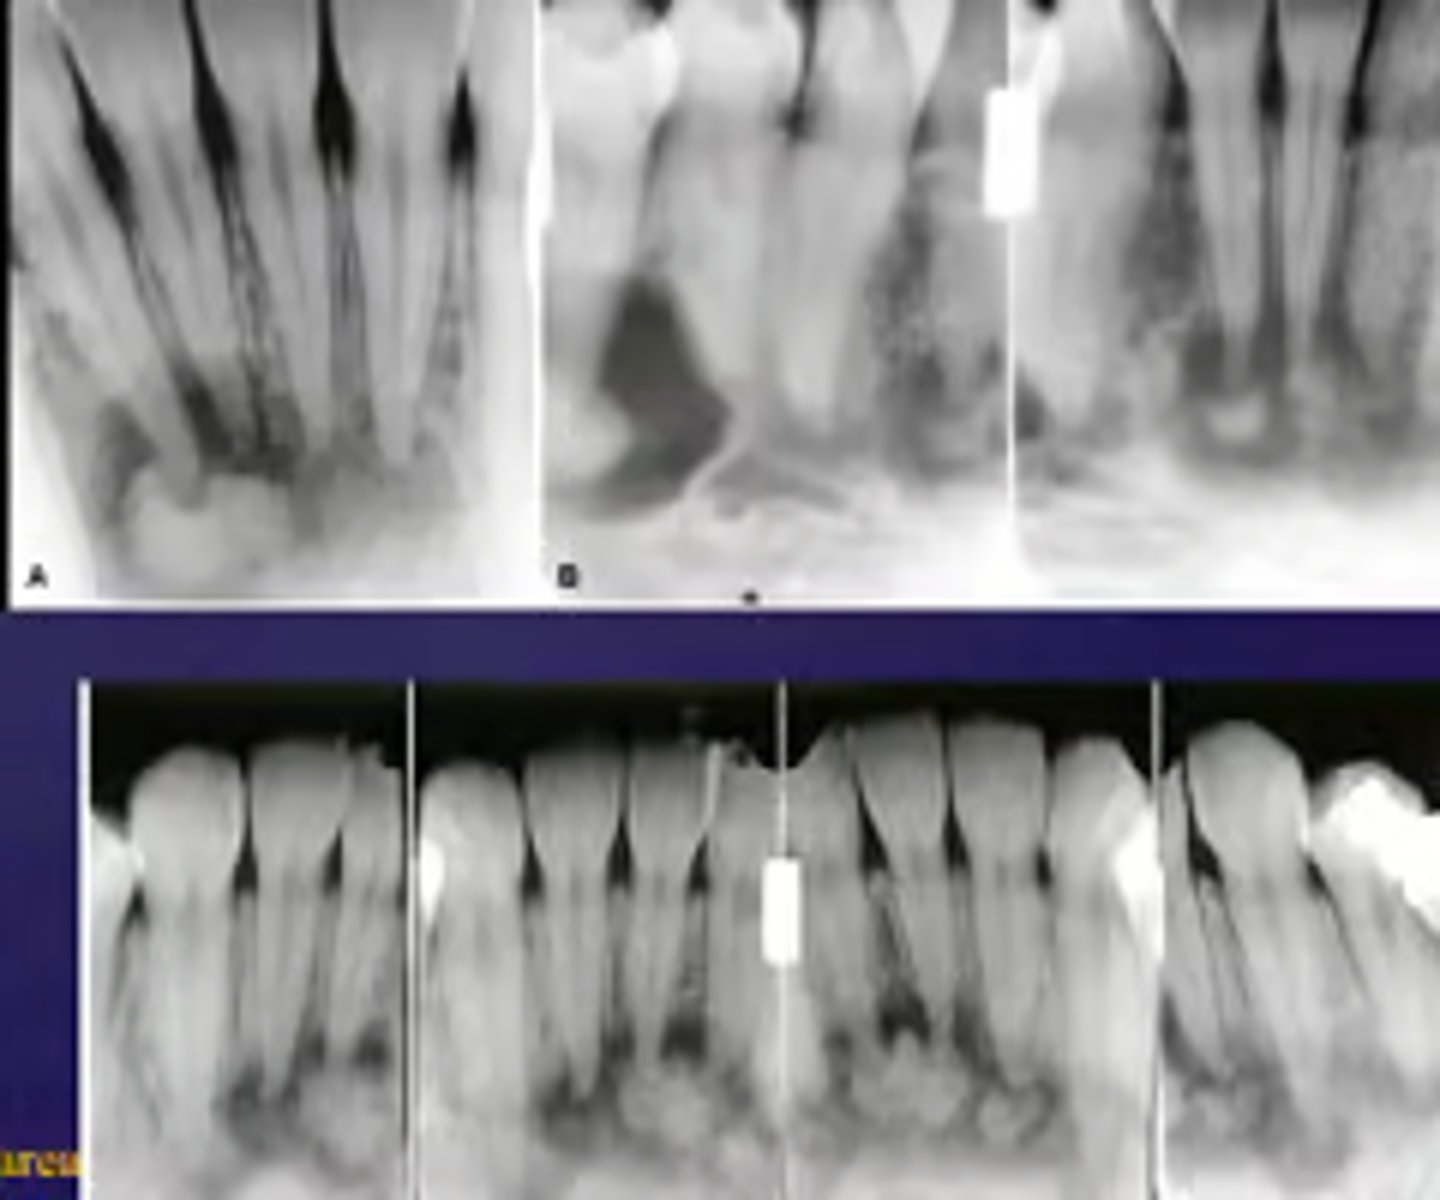

How would you describe the following lesion?

Multiple mixed density periapical target-like entities

The teeth are vital. What category would you put this lesion into?

dysplasia (PCOD)

what could be a differential diagnosis for this lesion?

A. radicular cyst

B. periapical granuloma

C. PCOD (stages 2/3)

D. apical rarefying osteitis